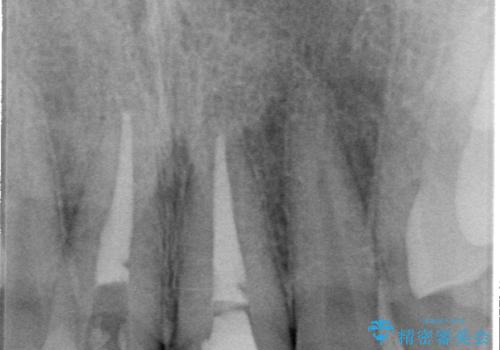

- 以前、保険診療で治療を受けた前歯の見た目が気になるとのことで来院された患者様です。

転倒時に前歯2本が折れてしまい、すでに根管治療(神経の治療)が行われている状態でした。

診査の結果、噛み合わせが深い「ディープバイト」の状態であり、下の前歯には叢生(歯並びのデコボコ)も認められました。

噛み合わせを改善するための矯正治療をご提案しましたが、患者様のご希望により矯正治療と根管治療の再治療は行わず、ファイバーコア(土台)+オールセラミッククラウンによる補綴治療を選択しました。